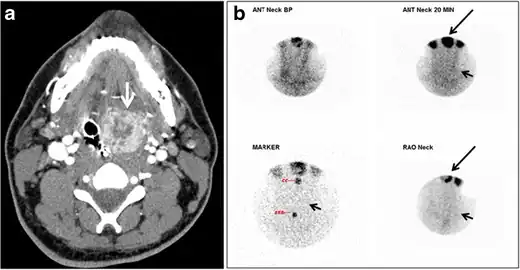

Fig. 8. A 48-year-old male patient post total thyroidectomy with PTC recurrence. a Transverse greyscale ultrasound of the neck demonstrates a left thyroid bed heterogeneous, predominantly hypoechoic irregular lesion with calcifications (white arrow). b A spot image of iodine 123 total body scan of the neck demonstrate a focus of abnormal radiotracer uptake at the left thyroid bed (Black arrows) between the annotated markers. c Enhanced axial CT scan of the neck demonstrates an enhancing large left thyroid bed mass (white arrow) with no calcifications. The lesion exerts a mass effect on the oesophagus (black arrow) and is inseparable from the trachea.[1] -